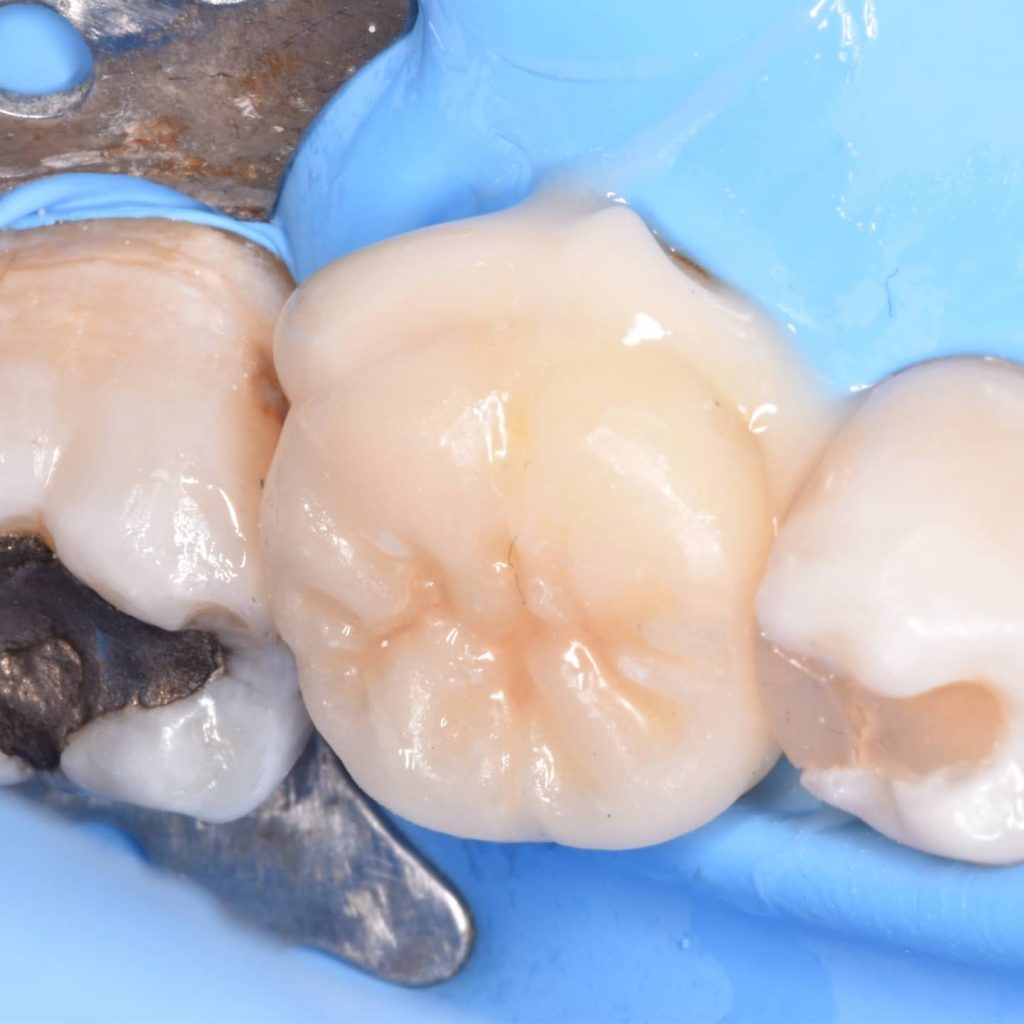

Tooth prepared to cementation by :

1_Isolation

2_sandblasting

3_phosphoric acid 37% and rinse

4_ bond application without curing

Put the cement materail and go for cementation

Immedait after cementation